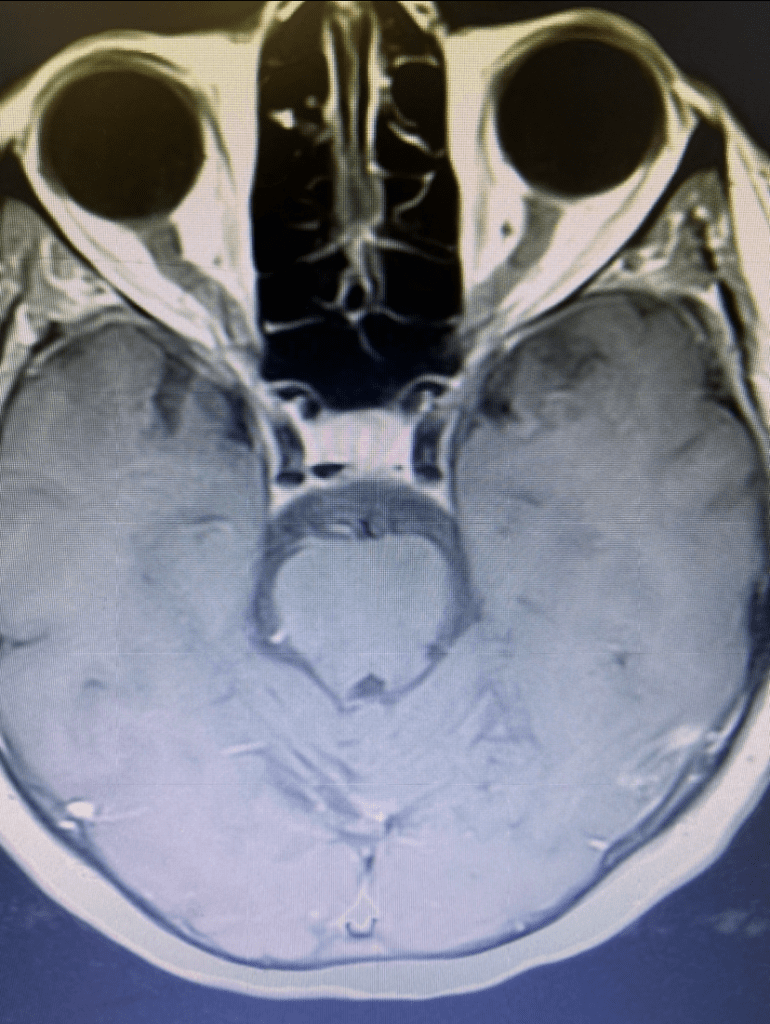

Subsequent to this, she underwent Gamma Knife treatment of the cerebellar AVM (figure 1) with Dr. Michael Brisman. She had no subsequent problems. Subsequent imaging showed that the AVM was starting to thrombose. She was then lost to follow up for many years.

Figure 1. Axial MRI with contrast at the time of gamma knife treatment showing the tightly conformal 50% Isodose line contoured around the AVM of the posterior superior cerebellar vermis.